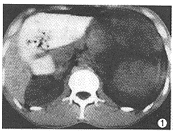

CT检查: 左肾下极见16cm×10cm×16cm巨大囊实性肿块,CT值20.1~48.6HU,肿块边界清 楚,占据左半腹腔(图1),左肾盂轻度扩大。增强后肿块实质部分有轻度强化,CT值62.5H U,可见完整包膜(图2)。右肾无异常,无肿大淋巴结。CT诊断:左肾巨大占位病变,肾母 细胞瘤可能性大。

图1 CT平扫显示腹腔左侧约16cm×10cm×16cm巨大囊实性肿块,CT值20 .1~48.6HU,肿块边界清楚 图2 CT增强扫描示肿块与左肾相连,实质部分有轻度强化,CT值62.5HU ,可见完整包膜。右肾正常